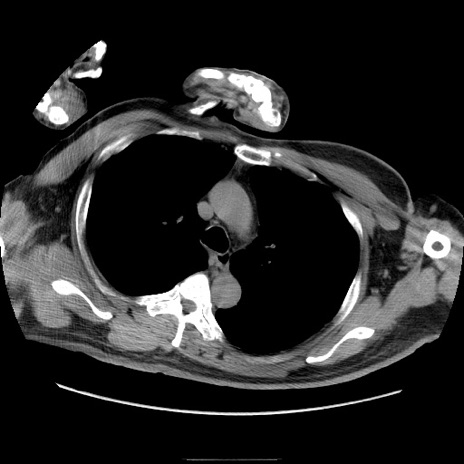

症例22(横断像)

【症例】50歳代男性

【主訴】腹痛

【現病歴】AVMからの被殻出血のため回復期リハ病棟入院中。 本日午後3時頃急に下腹部痛が出現した。

【既往歴】AVM、被殻出血、虫垂炎、高血圧

【身体所見】意識晴明、左半身不全麻痺、会話の理解は良好、36.5°C、腹部:膨隆、全体に板状硬、下腹部正中に圧痛点あり、反跳痛-、筋性防御不明、右下腹部にope scar

【データ】WBC 9400、CRP 0.06